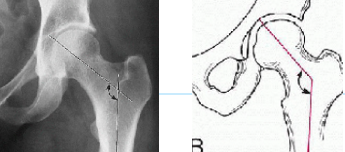

Q what is the name of this measurement? and what is the average + range?

A: Hadley's S Curve

assesses for subluxation by looking for a smooth, continuous curvilinear line. No average or range is specified.

A: Macnab's Line

assesses for impingement by a line drawn parallel to the inferior endplate.

This line should not intersect the SUP artic process below it.